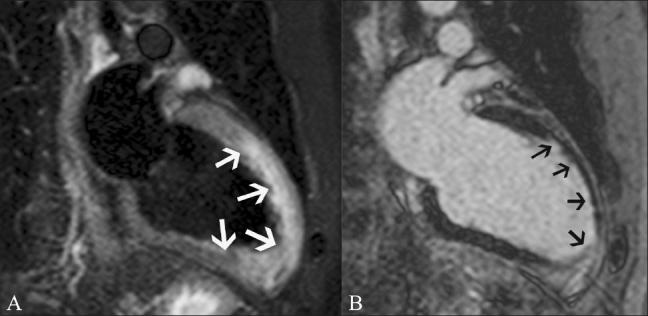

磁共振成像在评估心电图ST段抬高患者中的应用价值。

Utility of magnetic resonance imaging in the evaluation of patients with ST segment elevation on an electrocardiogram.

ST segment elevation is an important electrocardiographic (ECG) change that is typically found in acute myocardial infarction, but may also be seen in a variety of other conditions. MRI plays an important role in the evaluation of these patients. MRI not only establishes the diagnosis, which is essential for appropriate management, but also helps in the assessment of other factors that are important for risk stratification. In this review, we discuss the common and uncommon causes of ST segment elevation and the role of MRI in the evaluation of these disease processes.

摘要